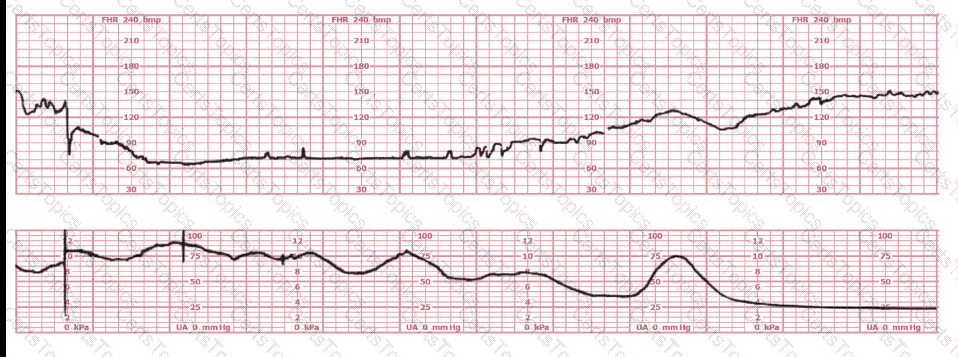

A nulliparous woman at term presents with leaking fluid. Rupture of membranes confirmed. After 6 hours she is completely dilated, +2 station, has been pushing 2 hours with oxytocin at 10 mU/min. The fetal tracing is shown. What is the next step in management?

A woman in labor has been pushing for 4 hours. For the last 2 hours, there have been recurrent variable decelerations. Variability has evolved from moderate to minimal. Cervical exam is 10/100%/+2, fetal head OP. There has been no fetal descent for the last 45 minutes. Based on the tracing shown, the most reasonable approach is

Based on the fetal heart rate tracing shown, the expected fetal pH would be:

Based on the tracing shown, the first action should be to